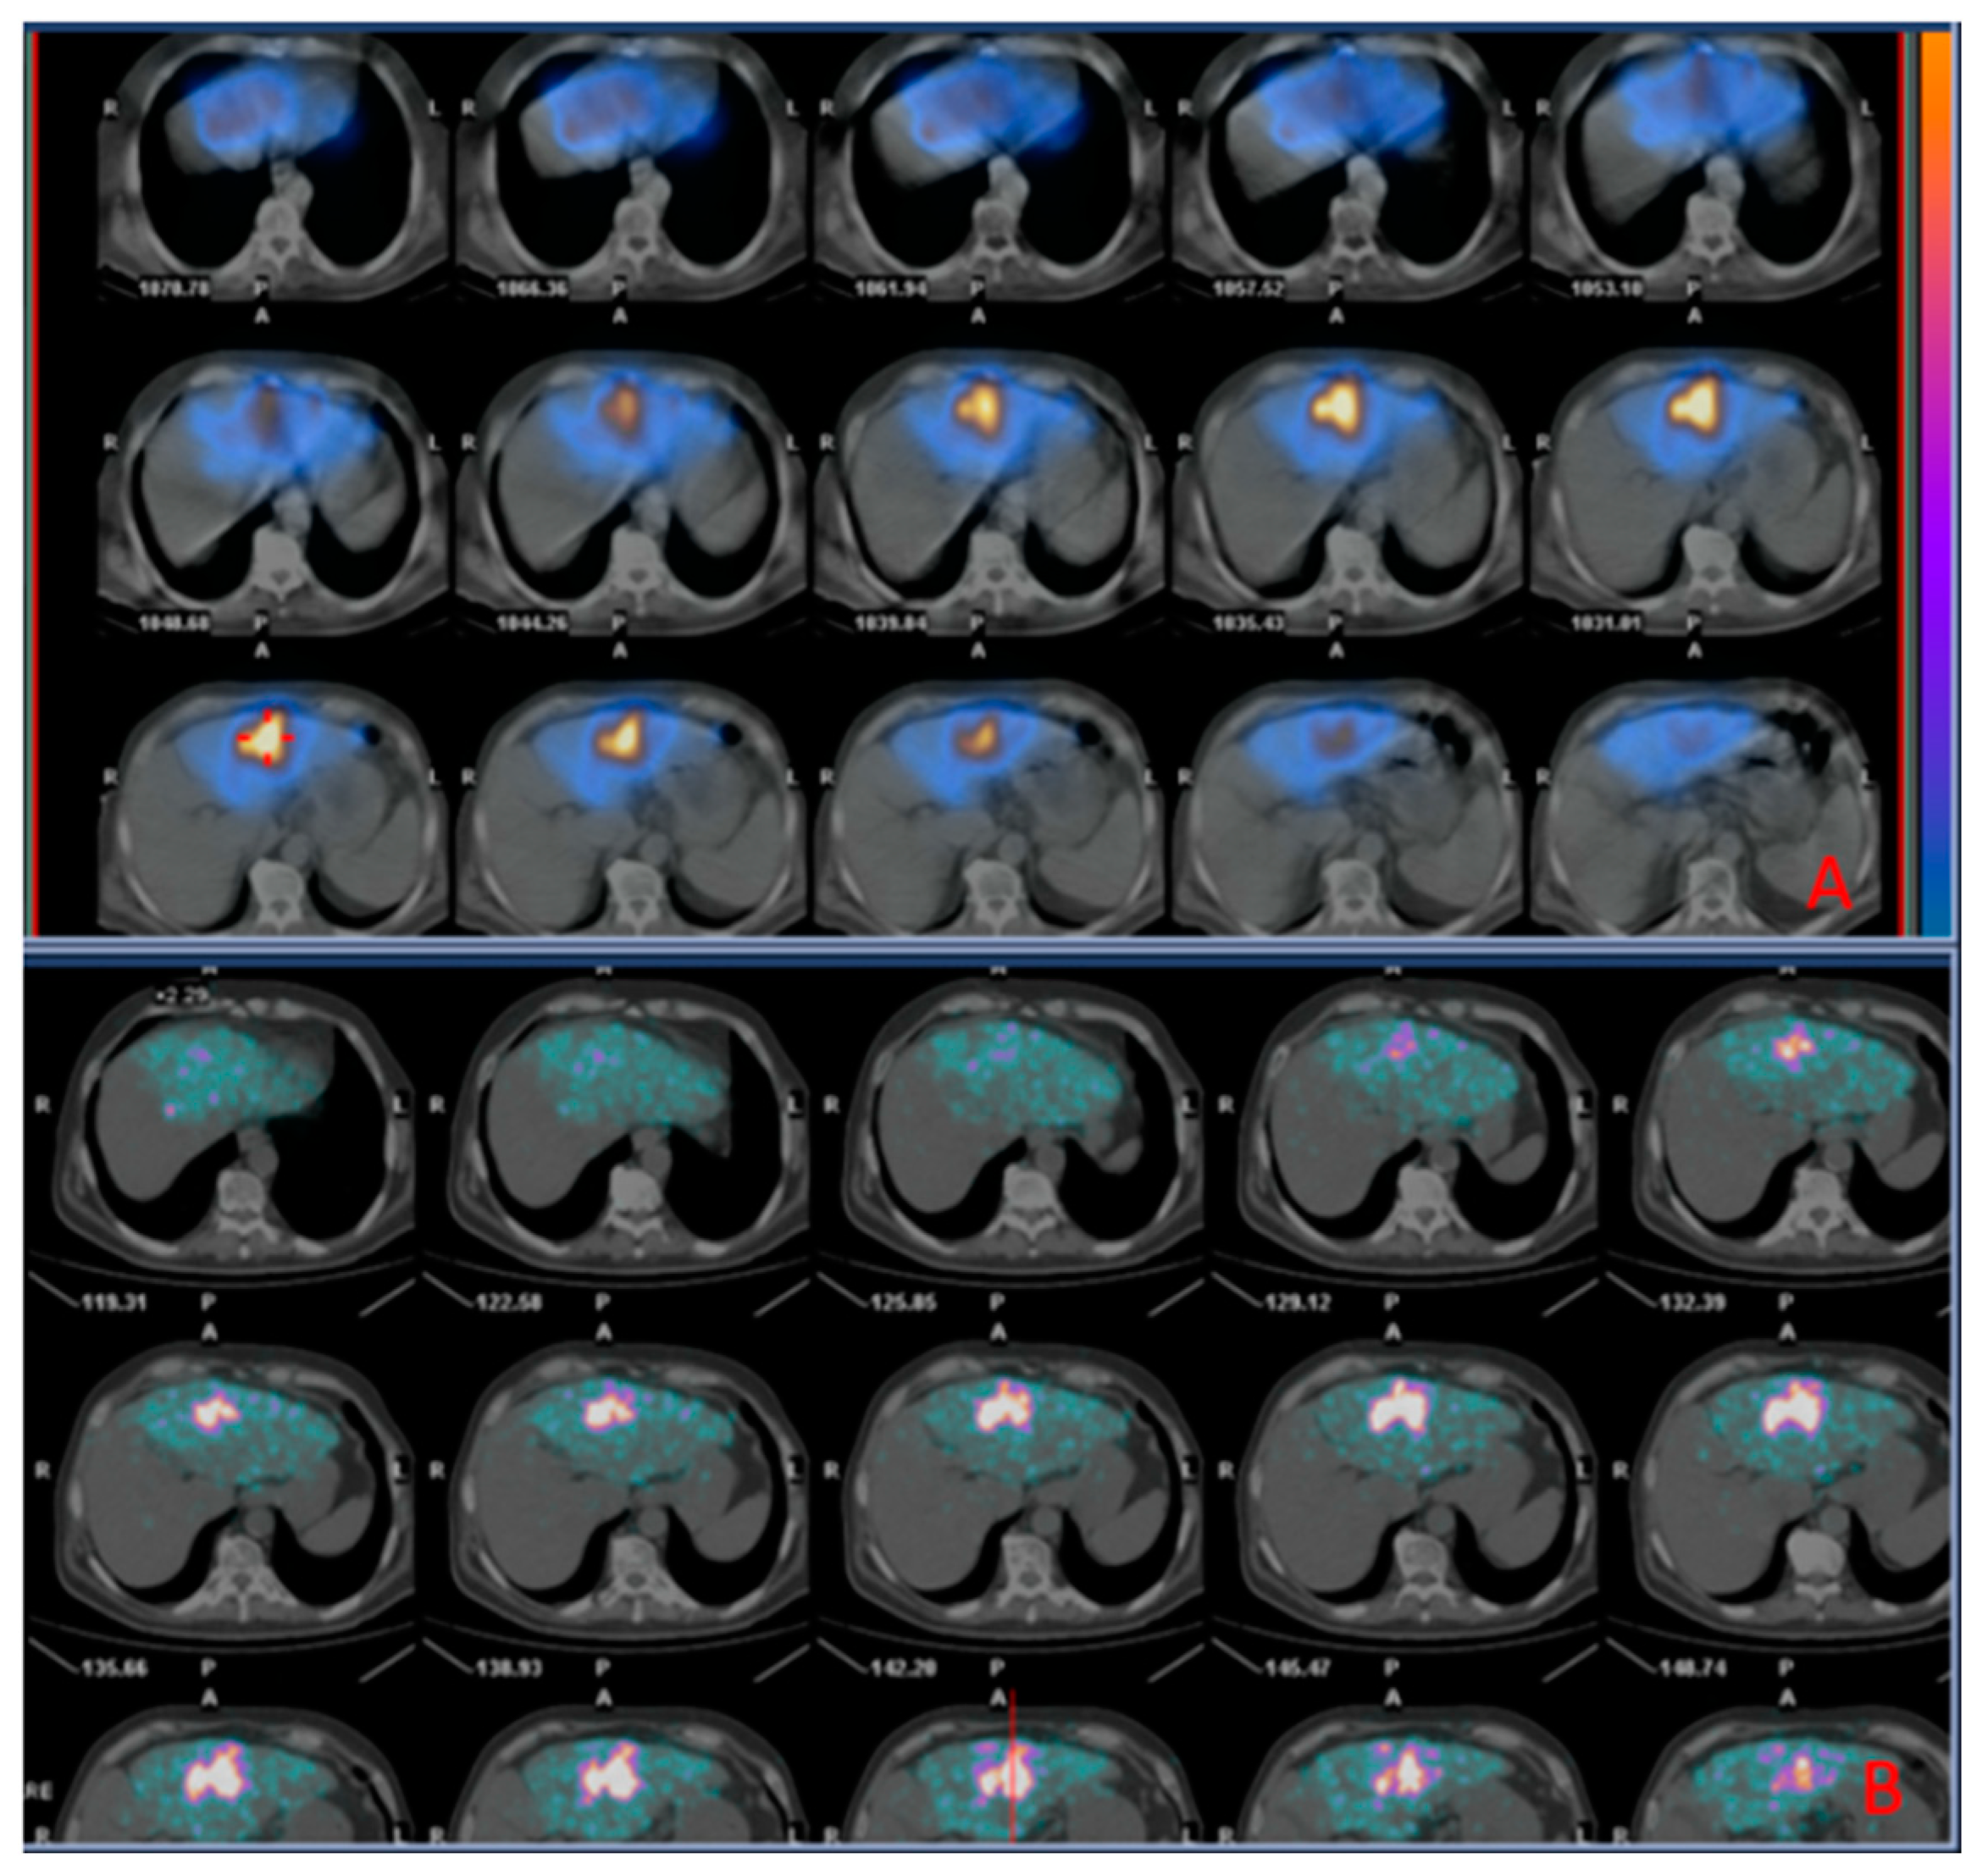

Patients with liver metastases from CRC receiving additional treatment demonstrated a longer OS than patients receiving only TARE (23.50±19.76 months vs. 8.54±5.31; p=0.018). There was a direct correlation between injected activity at TARE and OS (R=0.55, p=0.034) and between mean activity reaching the tumor and OS (R=0.812; p=0.008). A representative case of a patient with CRC liver metastasis treated with TARE is shown in Figure 1.

Figure 1. Images of a patient undergoing radioembolization of a hepatic metastasis from colorectal cancer. A: SPECT/CT images (diagnostic phase) 2h acquired after administration of 99mTc-MAA; B: PET/CT images (therapeutic phase) acquired 2h after administration of 90Y theraspheres, showing successful distribution of 90Y theraspheres matching that of 99mTc-MAA in the diagnostic phase.